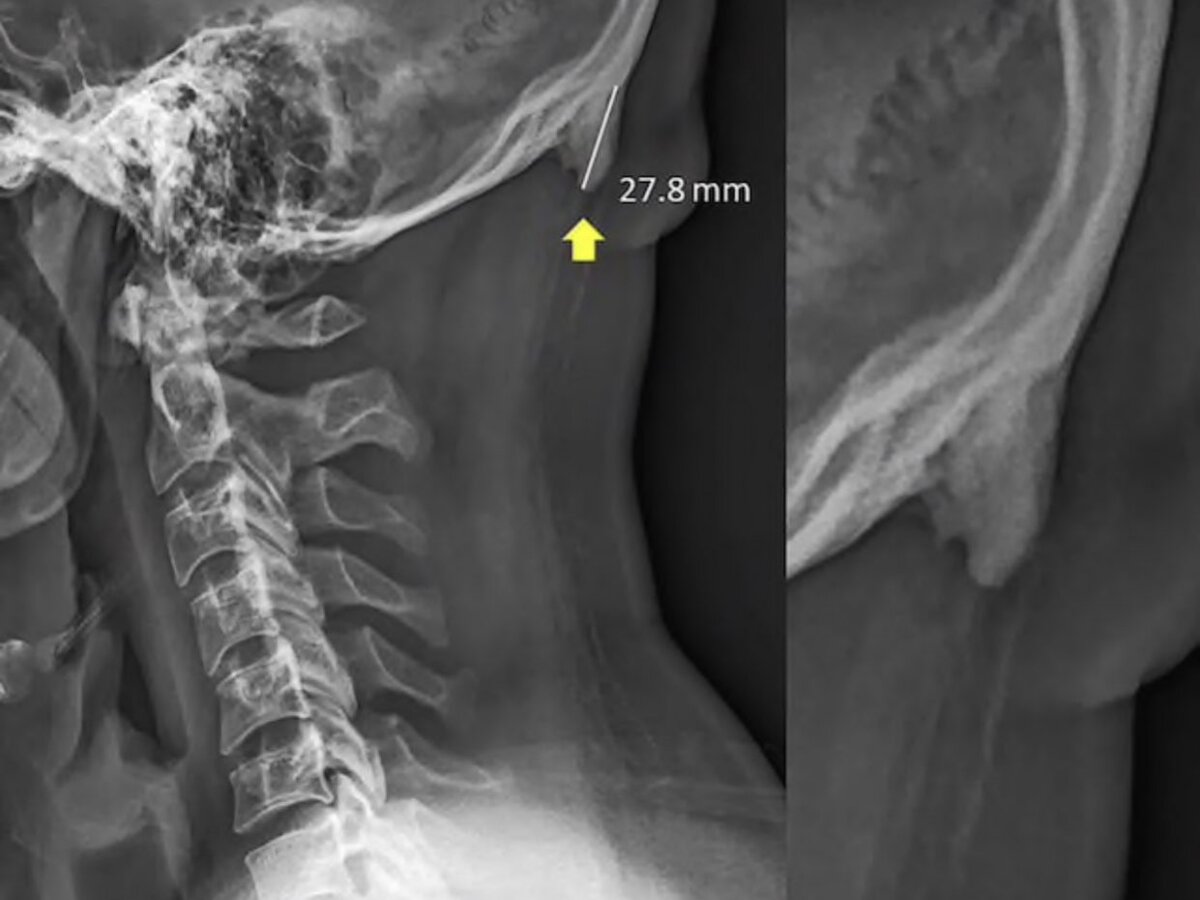

Учёные пришли к выводу, что человек, который постоянно наклоняется над смартфоном, может столкнуться с проблемой: от одной и той же позы над шеей появляется нарост в виде костной выпуклости.

Исследования показали, что треть населения имеет изменения костных тканей. Более того, с такой проблемой начало сталкиваться более молодое население, чем прежде.

Учёный объяснил, что причиной тому служит поза, в которой человек находится, а именно наклоняется к своему планшету или смартфону. К сожалению, современные технологии заполонили нашу жизнь, и очень сложно решить проблему, т.к. отказаться от них просто невозмозжно.